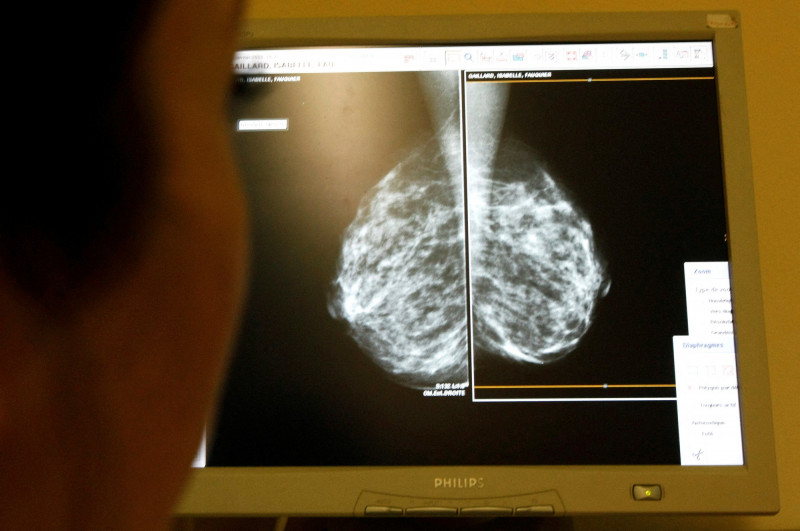

瑞典10萬人試驗 AI 助功判讀乳癌早期發現率多9%

〔編譯管淑平/綜合報導〕人工智慧(AI)技術正愈加被應用於輔助臨床診斷,全球首份對AI輔助判讀例行乳癌篩檢影像的隨機對照試驗顯示,AI有助於早期發現乳癌,在例行篩檢揪出的病例比對照組多9%,同時,女性在日後兩次例行篩檢之間才被診斷出乳癌的比率也比較低。

《衛報》、《法新社》1月29日報導,這項在醫學期刊《刺胳針》(The Lancet)發表的研究,以2021年4月到2022年12月間接受例行乳癌攝影的逾10萬名瑞典女性為對象,隨機分為兩組:一組由一名放射科醫師在AI輔助下判讀影像;另一組依照歐洲標準流程,由兩名放射科醫師共同判讀。

結果顯示,AI組在篩檢時檢測出乳癌比例明顯較高,有81%乳癌病例是在篩檢時被發現,相較之下,對照組為74%。之後兩年內,AI組被診斷出乳癌的比率,比對照組低12%,也就是在兩次例行篩檢之間被診斷出癌症,稱為「間隔癌」,通常格外危險,AI組每1000名女性約有1.55例在此期間診斷出乳癌,對照組為1.76例。此外,AI組中侵襲性較高的乳癌亞型病例比率,也比對照組低約27%。

這是全球首份探究AI輔助乳房篩檢完成隨機對照試驗,此為評估效果的黃金標準。研究主要作者、瑞典隆德大學放射診斷醫學副教授朗恩(Kristina Lang)表示,AI輔助乳房攝影可減少放射科醫師的負擔,並協助在早期檢測出癌症,包括早期發現侵襲性亞型,不過,將AI導入醫療照護必須「謹慎」為之,並且持續監測。